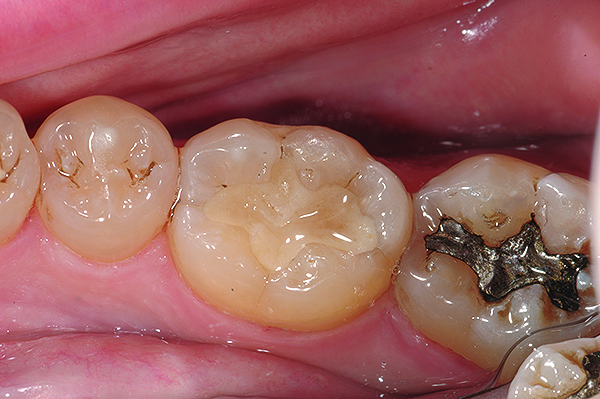

Fig 4 and Fig 5. Occlusal (Fig 4) and buccal (Fig 5) 42-month recall views of the Class I and Class V GIC restorations placed with bulk-fill EQUIA technique.

Figure 4

Figure 5